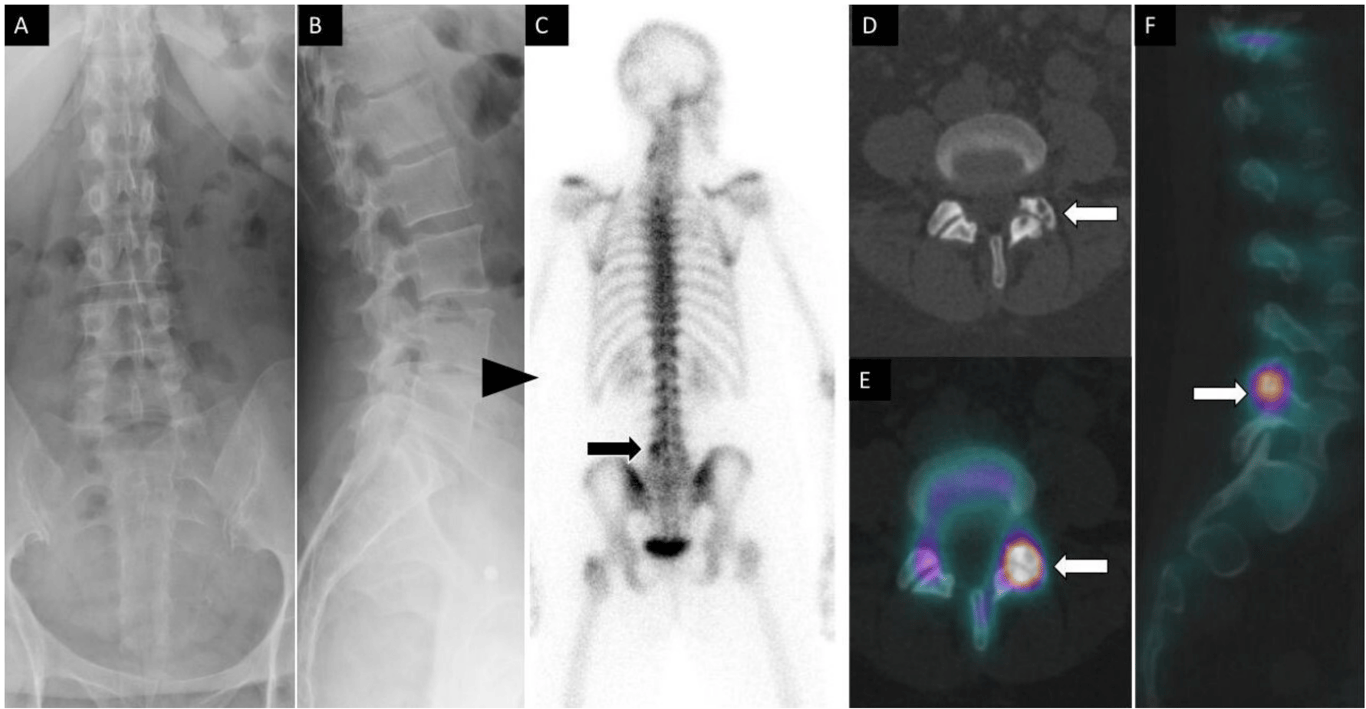

A 49-year-old man had a history of tonsillar squamous cell carcinoma and low back pain. Sagittal T1 (A) and STIR (B) magnetic resonance images show low T1 and high T2 signal changes within the L3 vertebral body (arrows). Posterior planar 99mTc-MDP bone scan image (C) shows increased osteoblastic activity at L3 vertebral body. Coronal fused single photon emission computed tomography with computed tomography image (D) demonstrates an osteoblastic lesion within the right L3 vertebral body with associated sclerotic changes on computed tomography (E) compatible with metastatic bone lesion.